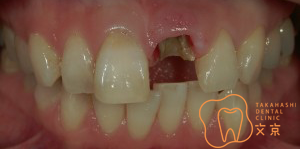

■前歯が折れてしまった、、、